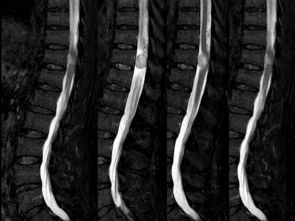

脊髓 脊髓,呈前后稍扁的圆柱体,全长粗细不等,位于椎管内,上端在枕骨大孔处与延髓相连,下端尖削呈圆锥状,称脊髓圆锥,圆锥尖端延续为一细丝,称终丝,终丝向下经骶。

脊髓的内部有一个H形(蝴蝶型)灰质区,主要由神经细胞构成;在灰质区周围为白质区,主要由有。

脊髓的内部有一个H形灰色神经组织,主要由神经细胞构成,外层为白色神经组。

位于脊柱中,呈长管状,色灰白。

其主要功能为传递脑与身体各部之间的讯息以及产生反射。